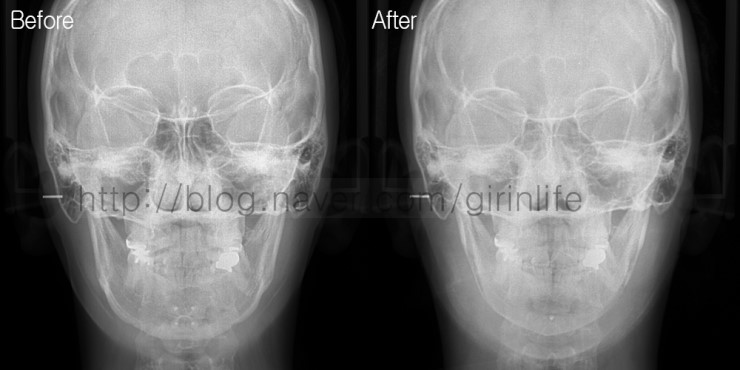

정면CT를 보면 앞턱에 티타늄고정장치가 보입니다. T절골을 하였고 그로인해 이차각이 동반되었습니다.

수술후 정면 엑스레이를 보면 고정장치가 보이지 않고 아래턱 라인이 갸름해진걸 확인할 수 있습니다.

엑스레이는 퇴원할때 촬영하기 때문에 부기로 인해 수술전보다 연부조직두께가 두껍습니다.